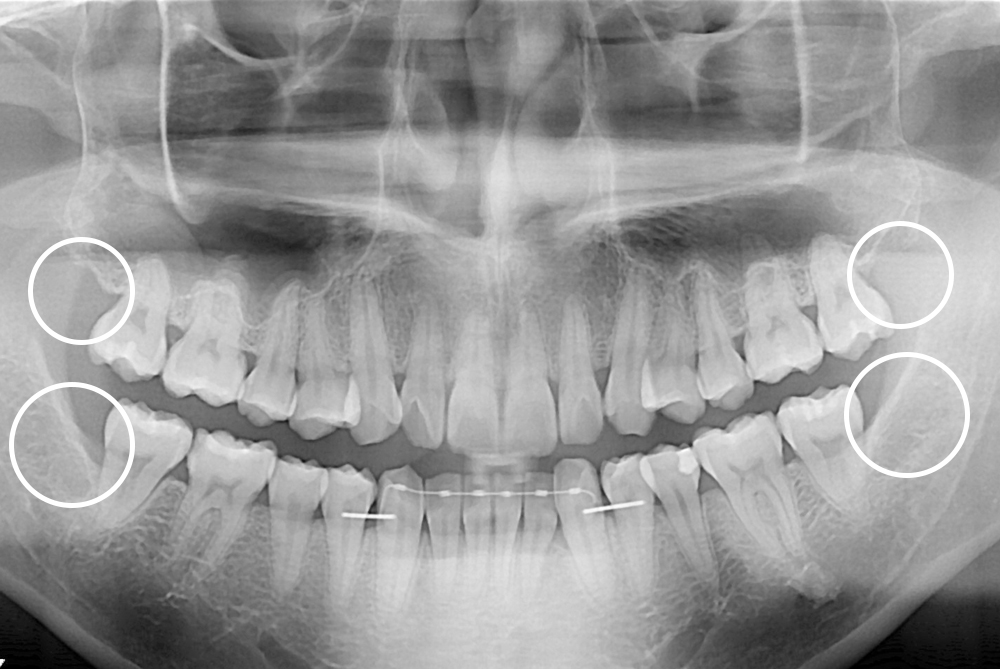

[사랑니] 매복 사랑니 발치

치료전 : 2018-01-02

세종치과는 구강악안면외과학 박사이신 원장님이 발치하는 치과입니다.